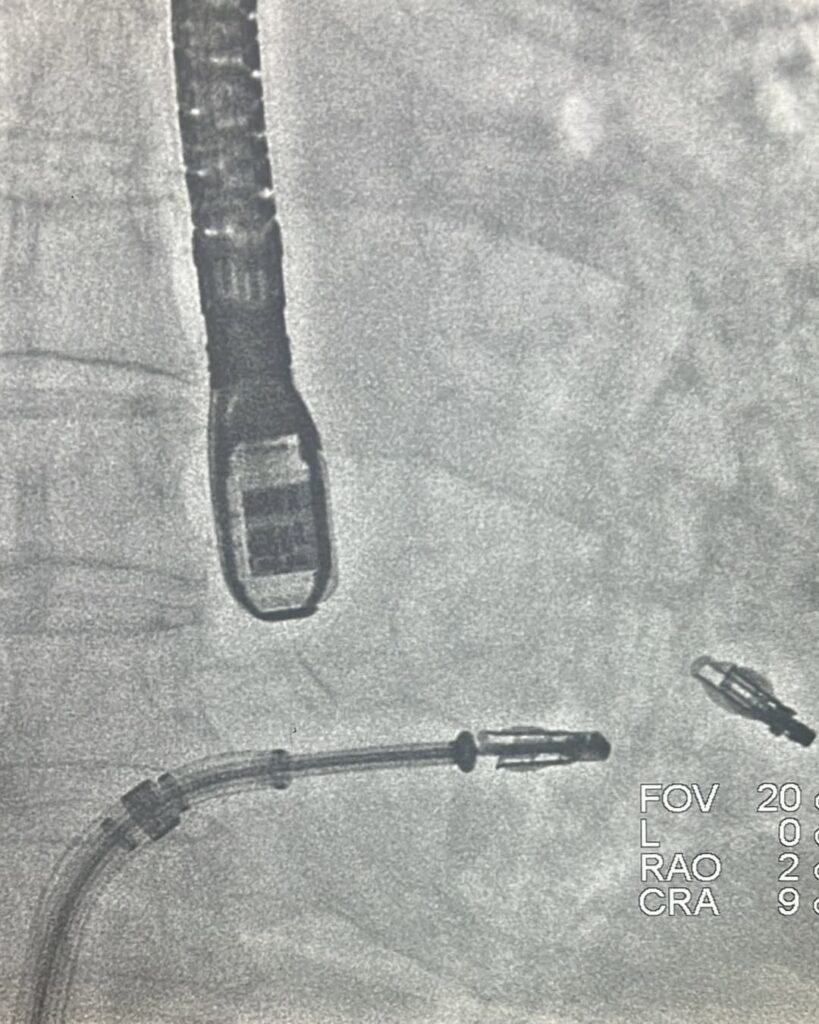

Özellikle aort kapak darlıklarında, anjiyo yöntemi ile kapak değişimi olarak bilinen TAVI uygulaması uzun süredir Ada Hastanesi’nde başarıyla uygulanıyor. Ayrıca mitral kapak yetmezliklerinde MitraClip, triküspid kapak yetmezliklerinde ise Triclip yöntemi etkili bir tedavi seçeneği olarak tercih ediliyor.

Ada Hastanesi, bölgede bir ilke imza atarak aynı seansta hem MitraClip hem Triclip uygulamasını iki hastada başarıyla gerçekleştirdi. Minimal invaziv yöntemlerin en büyük avantajı, kasık toplardamarından girilerek yapılması sayesinde hastada herhangi bir kesik veya cerrahi iz bırakmaması. Bu sayede hastalar yalnızca 1-2 gün içinde taburcu edilip kısa sürede normal yaşamlarına dönebiliyor.